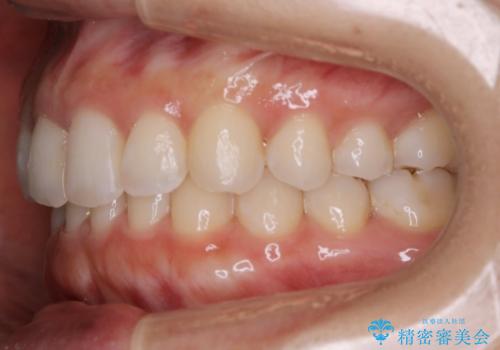

【非抜歯】下の前歯が1本少ない場合の矯正治療

- 前歯のガタつきを主訴に来院されました。

生まれつき下の前歯が1本少なく、その分のスペースを上の前歯がガタつくことで埋めているという状況でした。

上下それぞれのガタつきをとっていく過程で、歯1本分のスペースの差を、上顎の前歯のIPRで調整して並べる方法をご提案させていただきました。